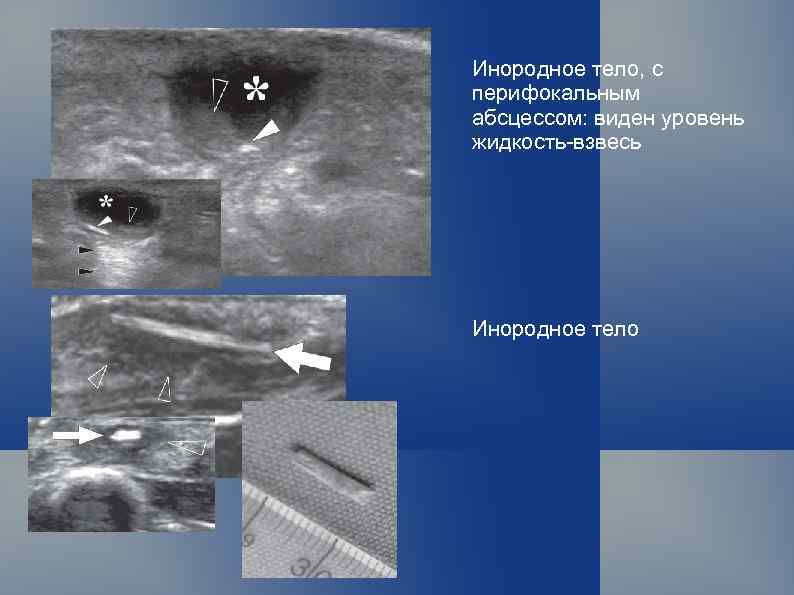

Инородное тело, с перифокальным абсцессом: виден уровень жидкость-взвесь Инородное тело